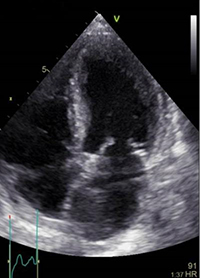

従来の超音波装置による診断画像 |

Vivid E95/90による高画質診断画像 |